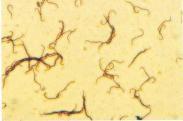

鉤端螺旋體病的腎損害治療

• 鉤端螺旋體病的腎損害